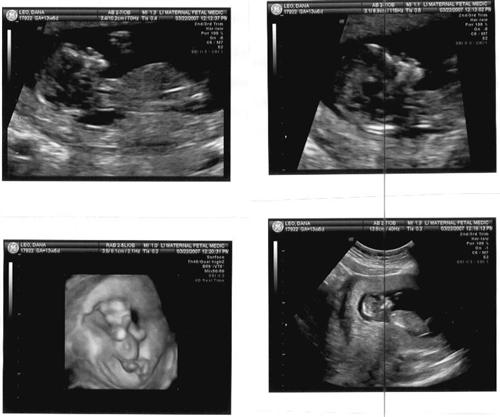

Just got back from the ultrascreen UPDATE w/pics

everything looked good! Just gotta wait for the bloodwork results.

Re: Just got back from the ultrascreen UPDATE w/pics

Wow! So different from the other ones! Your office offers 3-D? I don't think mine does!

Posted by Mrs. Patticakes

the ultrascreen dr. is high risk (dr. mastro) and has the 3d/4d machine...it was soo cool! But the baby was too small yet to get a good clear pic of the face on the 3d.

Posted by DanaRenee

The other ones look great, you can see the lips and nose so clearly!